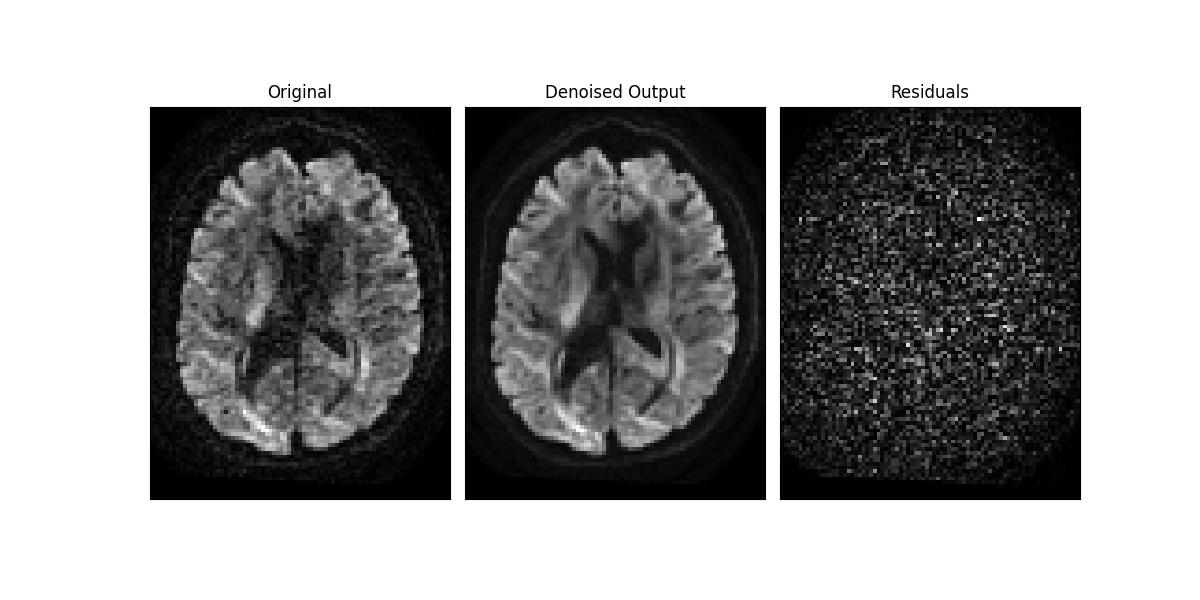

Now let’s visualize the output and the residuals obtained from the denoising.

Patch2Self preserved anatomical detail. This can be visually verified by inspecting the residuals obtained above. Since we do not see any structure in the difference residuals, it is clear that it preserved the underlying signal structure and got rid of the stochastic noise.